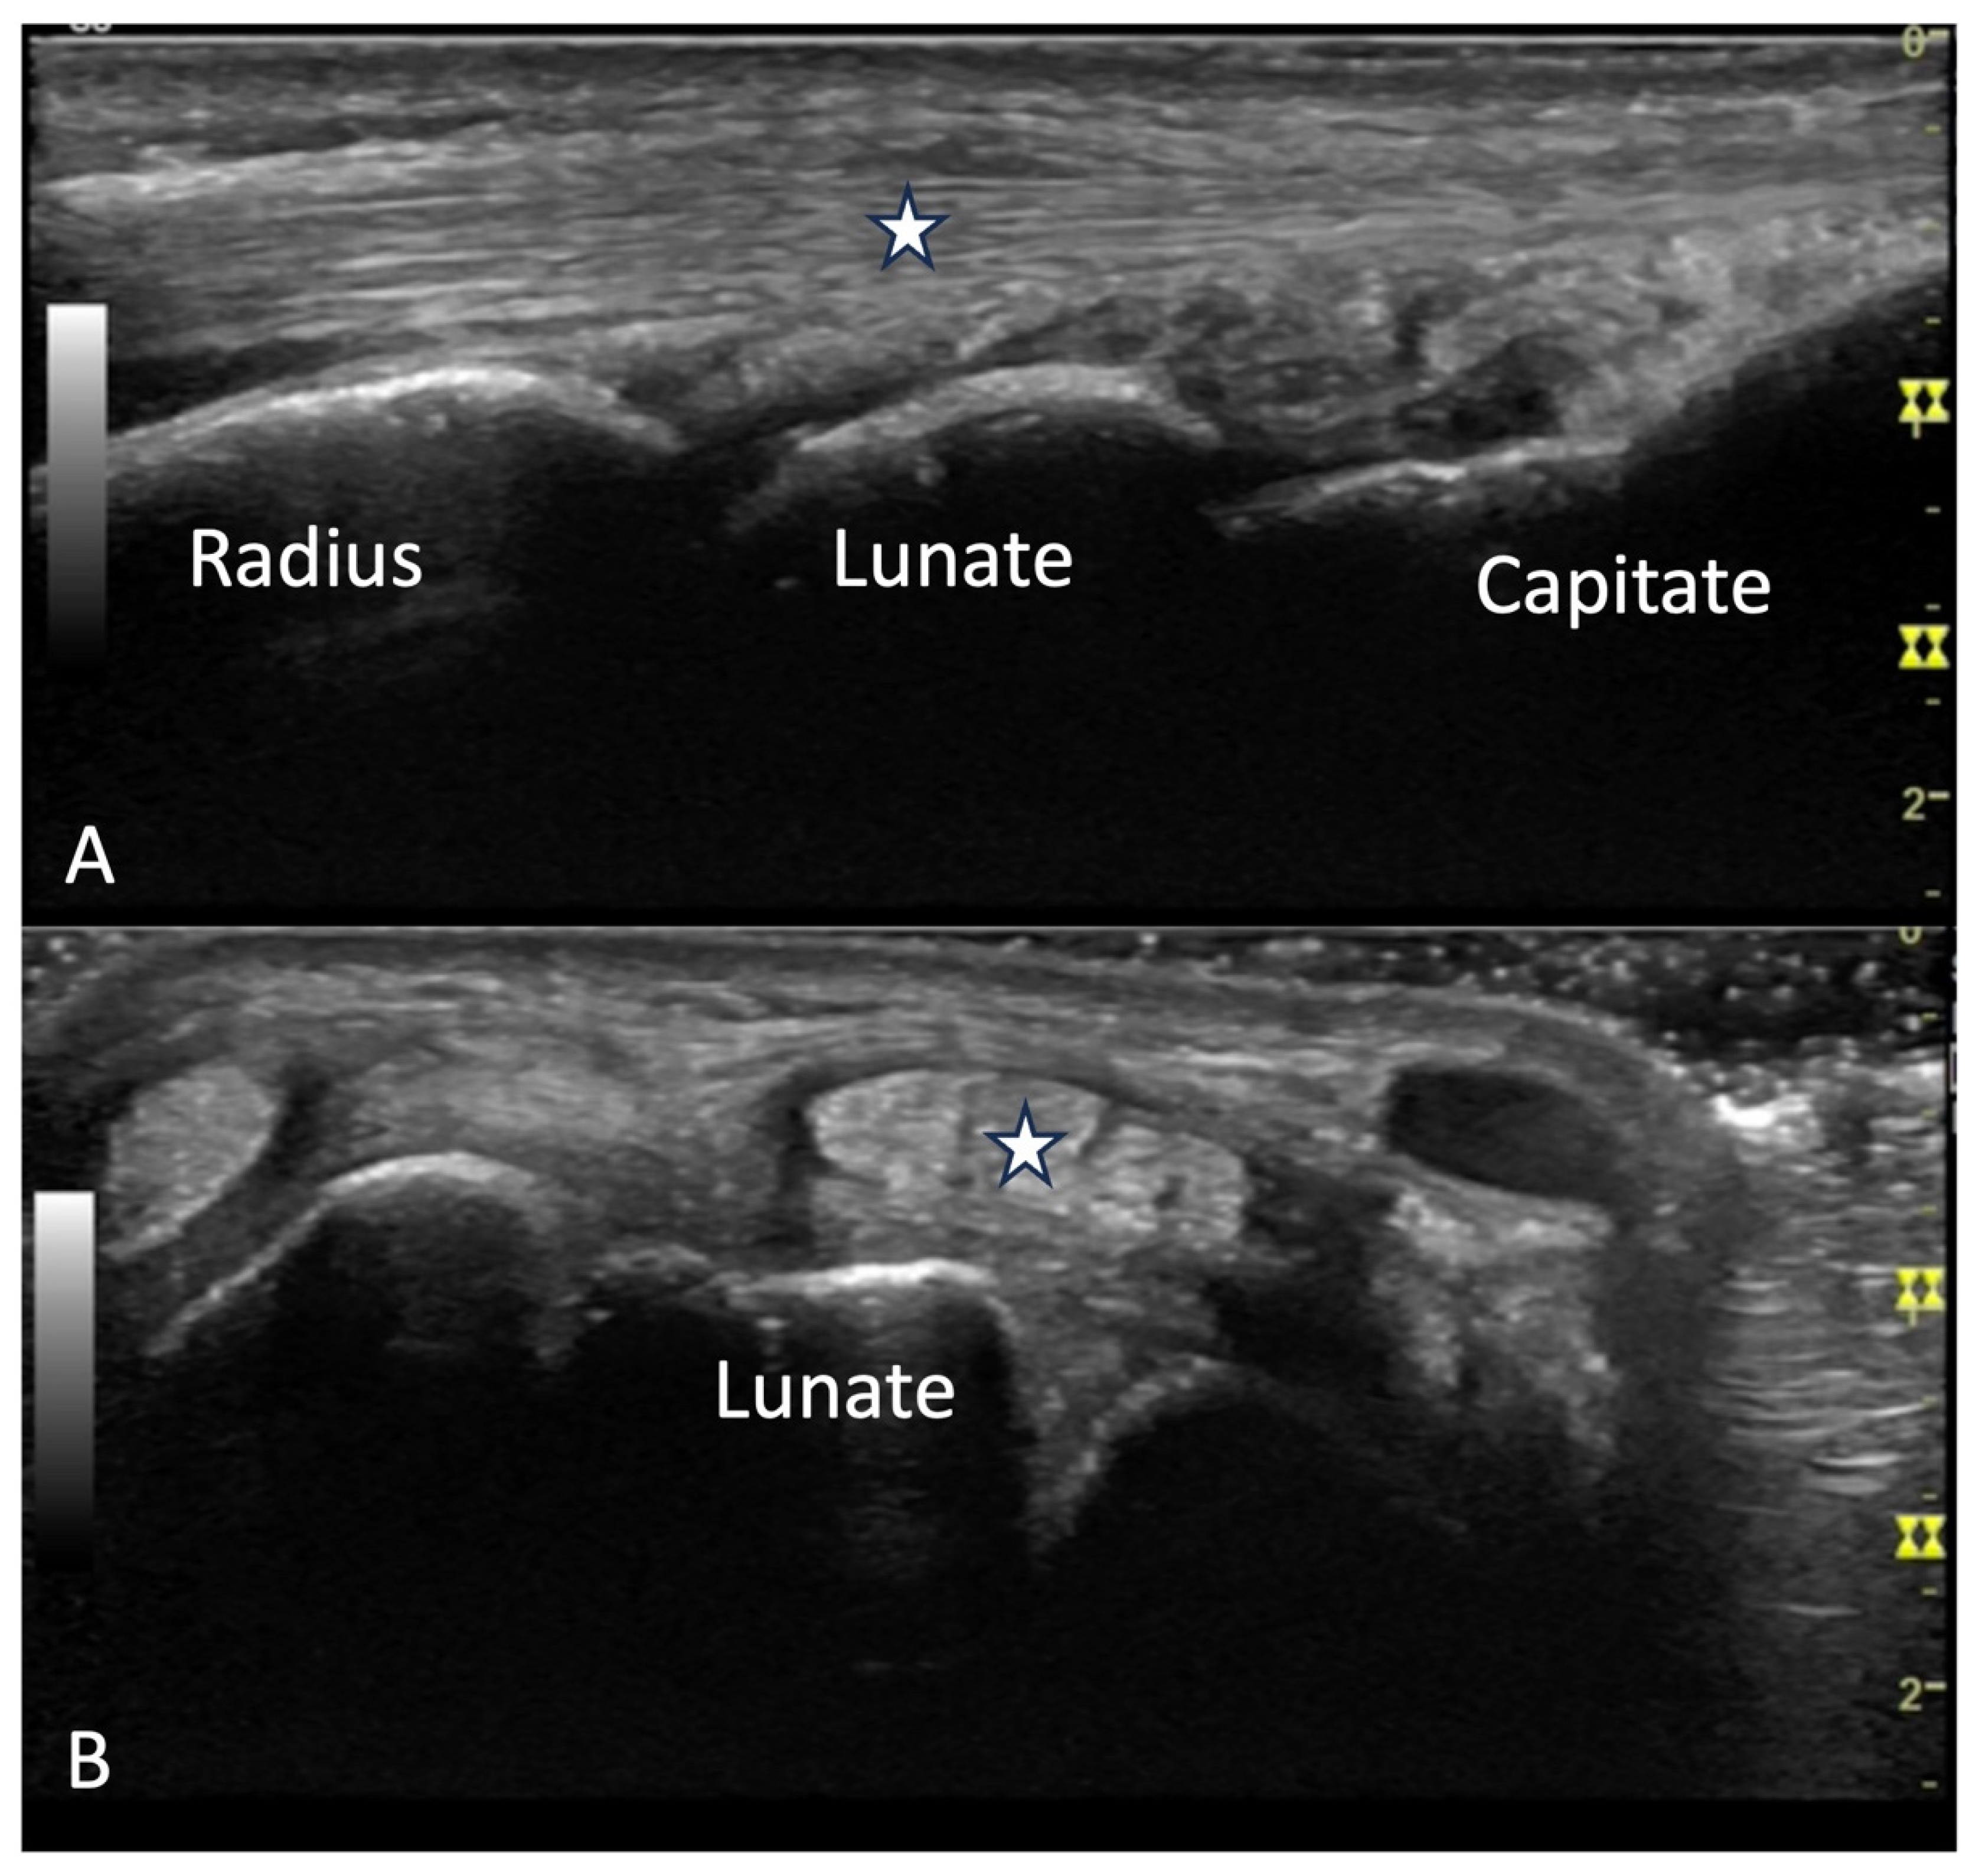

4.2. Evaluation of the Wrist

4.2.1. Dorsal Aspect

4.2.2. Volar Aspect